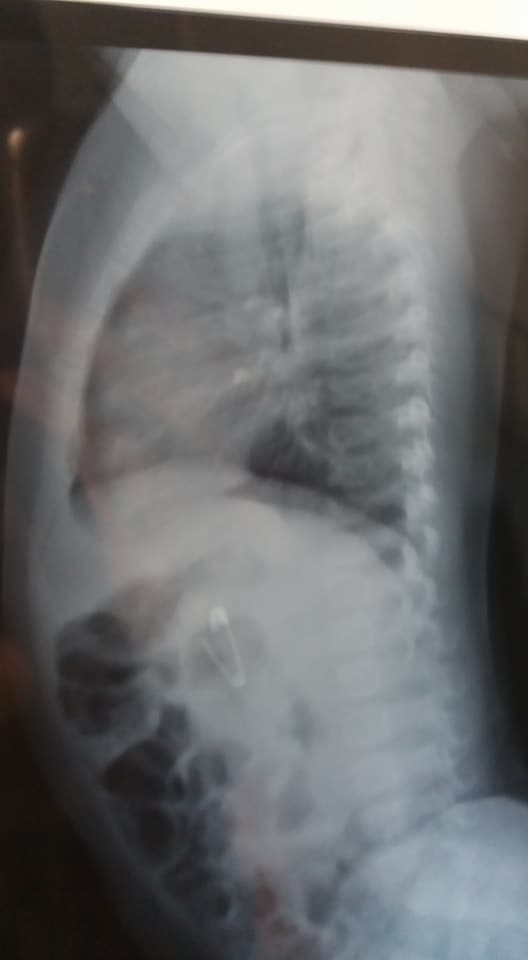

Já em Belo Horizonte, um procedimento de endoscopia e sedação do bebê foi realizado por uma equipe médica na tentativa de retirar o alfinete.

A angústia do casal aumentou quando foram informados pelos médicos que não era mais possível retirar o objeto, pois ele já havia migrado para o intestino do pequeno Isac e que havia um grande risco do alfinete perfurar o intestino.

Os médicos então precisaram esperar para o objeto saísse de forma natural, momento em que poderia arranhar o intestino do bebê e trazer sérias complicações a sua saúde.